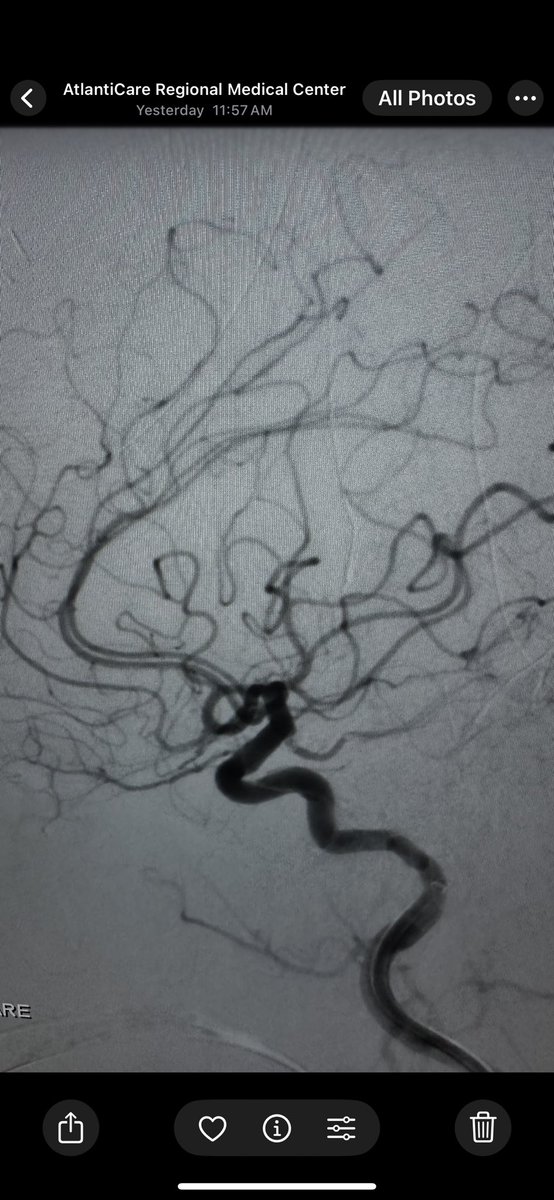

Inverted #rollercoaster technique to StrykerNeurovascular coil large SCA #aneurysm with temporary stent Terumo Neuro LVIS EVO CNS CV Section AANS Narration: Jaims Lim Advantages: protecting the neck without need for #DAPT (nuisance bleeding) pubmed.ncbi.nlm.nih.gov/32620576/